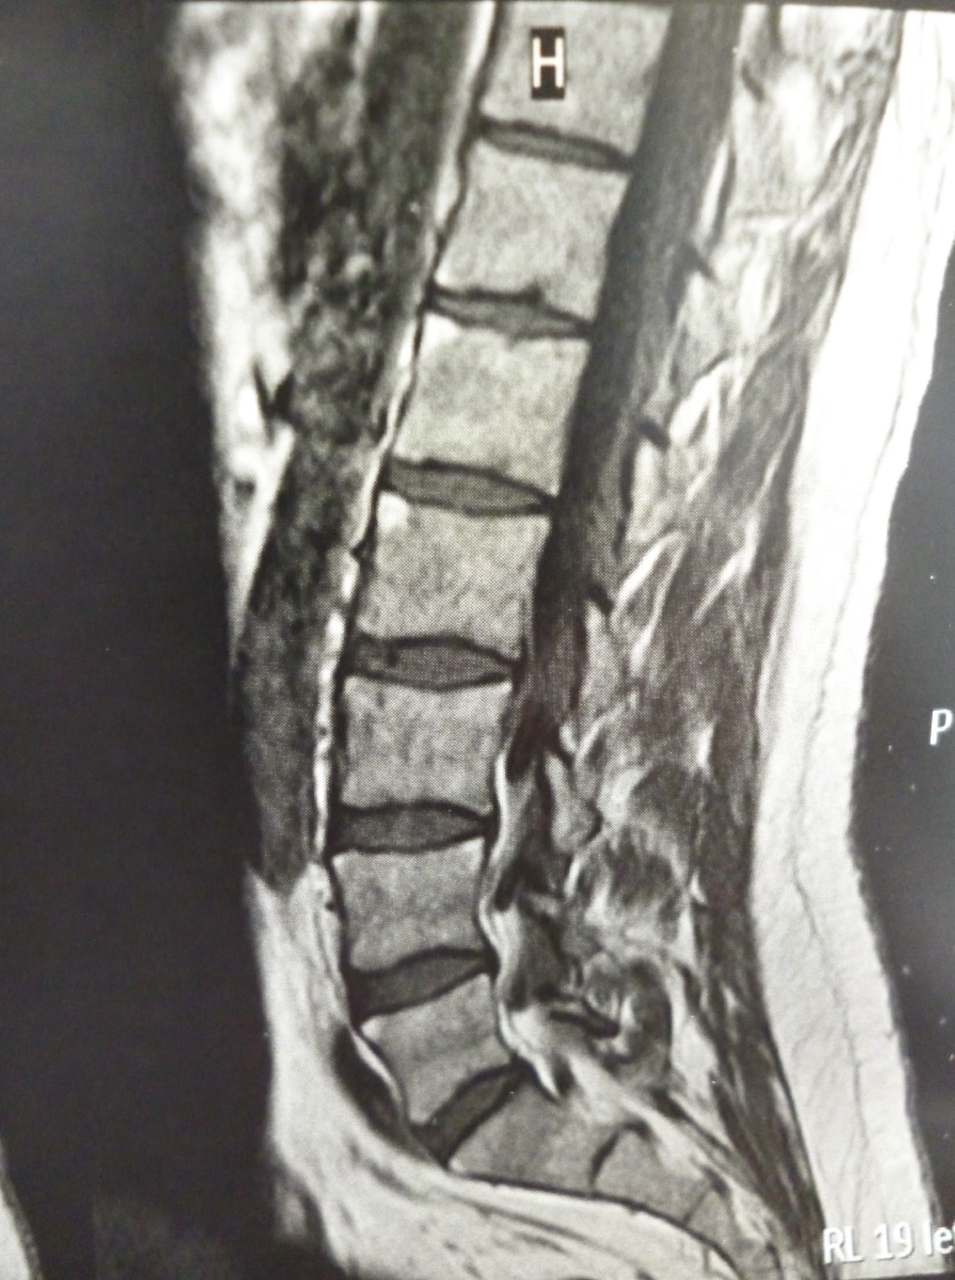

Homme de 38 ans ayant des lombalgies inflammatoires.

Quel est votre diagnostic ?

Devant des rachialgies chroniques restant inexpliquées, il est légitime de prescrire une imagerie par résonance magnétique (IRM) rachidienne, centrée sur la zone la plus symptomatique. Cet examen peut révéler des anomalies évocatrices de spondyloarthrite dont les plus fréquentes sont des coins vertébraux antérieurs œdémateux (flèches blanches). Cet examen a permis de faciliter le diagnostic de spondyloarthrite dans les formes radiologiquement négatives ; ce qui n'est pas rare à un stade précoce de la maladie. Son interprétation doit être faite par un radiologue expérimenté. La négativité de l'IRM ne permet pas d'écarter le diagnostic de spondyloarthrite.